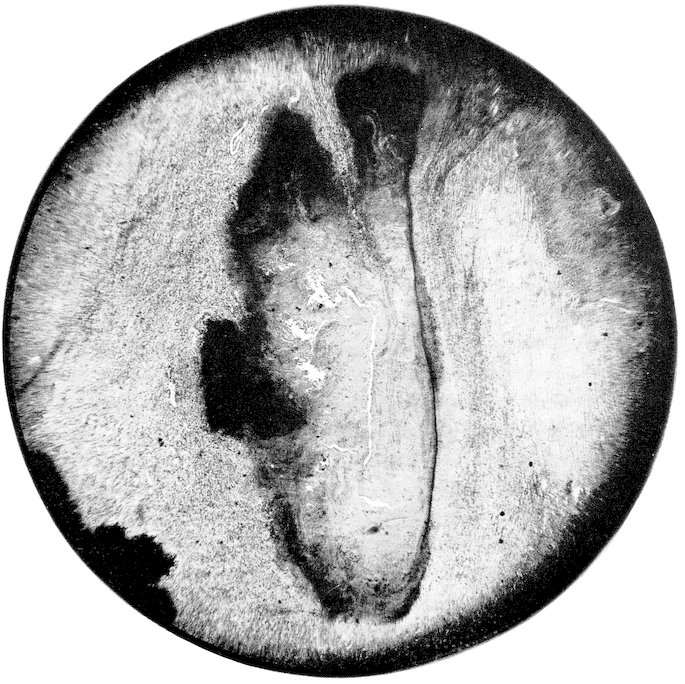

Some attention has been given to the study of diets for the wild specimens of our Garden, but no systematic observations have been made or records kept upon purely physiological subjects. Reference will be made at appropriate places to accepted comparative physiological facts, but our statistics permit additions to such knowledge only in a limited manner and in isolated instances. Doctor Corson-White has very ably summarized the diet, alimentary tract and physiology of the zoological groups with the pathology as found in our records.

A word might be added here as to the destruction of animals by injury from fighting and harassment by others in the cage. Fighting doubtless causes death, especially when males are together, but it is our experience that in cases of traumatic death search should always be made to see if the resistance of the dead animal had not been reduced by some disease. This is well illustrated in birds. Very frequently a specimen will come to autopsy with its head feathers plucked out, or with a billthrust in the wing or pelvic region. Such birds are not infrequently suffering from malaria, or heavy intestinal parasitism or from organic disease whereby the resistance and self-preservatory power has been decreased.

The foregoing survey of the approach to our subject reveals the multiplicity of factors which affect the study of comparative pathology. No one of them can be entirely omitted, no one is without some effect upon the origin and expression of disease, and no one is fully understood. Yet it is to be hoped that a study of our material, accumulated under routine conditions and uninfluenced by any experimental procedures, will demonstrate the natural response of various zoological groups to morbific agencies. Perhaps reactively some of the modifying 41conditions may thus be understood. It is also not unreasonable to expect that alterations observed as natural responses in a large number of specimens in nearly normal surroundings would serve as more reliable guides to investigative speculation than would changes in a few animals under artificial technical experimentation. We hope that the few facts we have been able to record may afford someone a basis for further biological studies. It is also to be hoped that something has been learned which in the end will afford an explanation of the diseases of man. Too great optimism in this direction should be guarded against because the human being is indeed an animal sui generis and, from the standpoint of normal conditions of nature, a wild animal.

The zoological classification found on pages 43–46 was compiled in 1903 by Dr. A. E. Brown on the basis of the British System. With a few exceptions the computations in the text are made on the basis of zoological orders since the number of specimens in families is often too small and the complications of so many different figures would be confusing. The tables will be found to correspond to the sequence of the classification. Dr. Corson-White has, however, used for her analysis the dietary groupings. A carnivore in her chapter implies strictly a meat-eater, in the rest of the book one of the zoological group Carnivora.